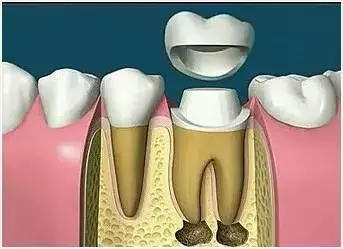

7.打樁 8.牙冠

1、為(wei) 咀嚼任務重的患牙加個(ge) 外套:由於(yu) 去除感染的牙神經和組織後,牙齒剩餘(yu) 的健康組織就不多,且牙齒沒有了營養(yang) 來源,牙齒會(hui) 變得很脆弱,咀嚼時容易折斷。如果做個(ge) 牙冠,就能為(wei) 牙齒加個(ge) “buff",讓牙齒得以繼續使用,治療後加以保護與(yu) 不保護,結果自然是不同的。

2、注意患牙的愛護:即便是有牙冠保護,畢竟是假牙,再相似也不是真的。所以在日常使用過程中需要多加愛護,比如說不要用牙齒吃過硬的螃蟹、排骨、甘蔗,也不要把牙齒當做啟瓶器、剪刀等工具,否則可能會(hui) 因為(wei) 咬合過大而導致牙冠繃瓷折裂。